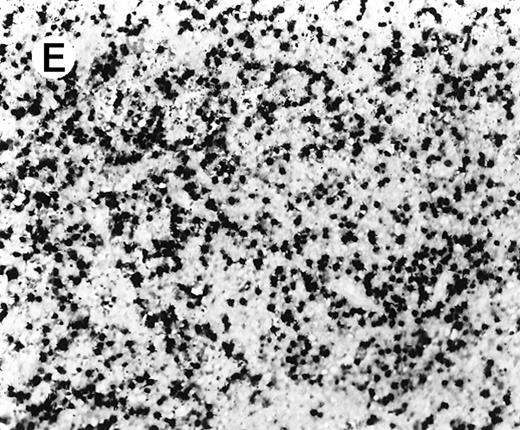

Staining for CD4 and CD8 in spleen from case 2.

(A) The lymphoid infiltrate in the spleen is predominantly CD8+. (B) Staining for CD4 highlights erythrophagocytic histiocytes, whereas the lymphocytes are negative. (C) The small lymphocytes express TIA-1. (D) They are BF1+ and are strongly EBER-1+ (E) (immunoperoxidase stained, hematoxylin counterstained, × 200).

ISH for EBV

In situ hybridization for EBV using the EBER1 probe showed striking positivity in the majority of the small lymphoid cells in all cases (Figure 4E). Correlation of the EBV positivity with the distribution of CD4/CD8 staining clearly indicated that the EBV-harboring cells were CD8+ in cases 2 and 5 (Figure 4E) and CD4+ in case 4 (Figure 5A-C). In addition, although an admixture of CD4+ and CD8+ cells had been previously noted in case 1, double staining for EBER1 and CD4 confirmed presence of EBV in the CD4+ population, with the CD8+ cells being clearly negative (Figure 6A,B). In the other 2 cases (cases 3 and 6), it was difficult to ascertain whether the CD4+ or CD8+ cells harbored the EBV, and double staining was not contributory.